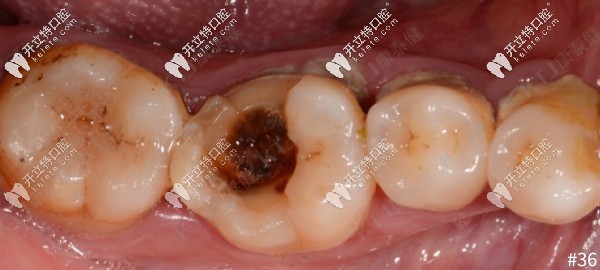

牙齒大面積缺損,用康泰健格萊美瓷嵌體修復(fù)案例分享

牙齒缺失牙齒修復(fù)牙齒嵌體修復(fù)發(fā)布時(shí)間: 2025-05-11

傳統(tǒng)的補(bǔ)牙是把齲壞的部分磨掉,補(bǔ)上材料完成的。但對(duì)于大面積缺損只是簡(jiǎn)單普通補(bǔ)牙并不能達(dá)到好的效果,今天來(lái)看一例康泰健格萊美瓷嵌體對(duì)大面積牙齒缺損的修復(fù)案例。